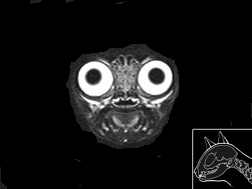

Atlas cérébral du chat IRMT2

IRM T2

31 coupes

Atlas cérébral du chat IRMT1

IRM T1

>> 31 coupes